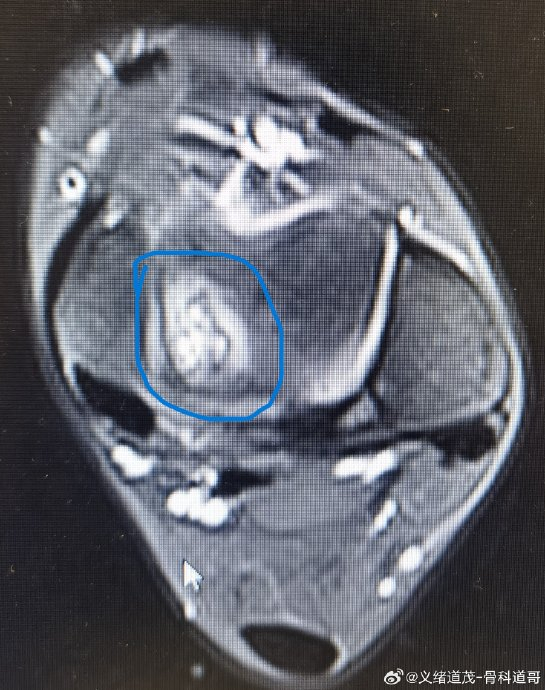

当CBA球星孙铭徽在2026年2月的比赛中遭遇90度崴脚被紧急送医时,核磁共振报告揭示了职业篮球运动员的噩梦——距腓前韧带撕裂;这一伤病如同隐形的利刃,曾斩断过NBA与CBA赛场诸多球星的征途。

孙铭徽(浙江广厦,2026年)

在俱乐部杯赛中抢断落地时右踝呈90度外翻,确诊距腓前韧带撕裂。队医当场将其背离球场,核磁共振显示其伤情需"以月计"恢复周期,这是他生涯首次遭遇毁灭性踝伤。球队卫冕计划因此蒙上阴影。